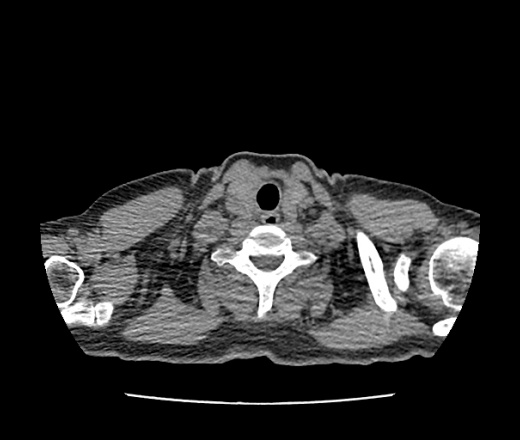

женщина , 45 лет, с температурой , кашлем, признаками ОРВИ, неделей ранее выполнялась рентгенография , по которой было заподозрено Са левого легкого. На кт - консолидация 6 сегмента с просветами деформированных бронхов, просвет сегментарного бронха не определяется . больше данных за пневмонию или Са? в s6 справа и s5 слева- фиброз ?

больше склоняюсь к пневмонии в s6 с ателектатическим компонентом.. интересно ваше мнение

Динамика нужна. Кт или рентген - как получится. ФБС нужно с цитологией.

В S6 рак - не самое частое явление, в тройках чаще. Пока, думаю, пневмония. В S5 слева фиброз, справа в S6 - неясно. Может разрешающаяся консолидация.

не понравились язычковые сегменты слева.

Слишком "круглит".

Cтавлю на рак.